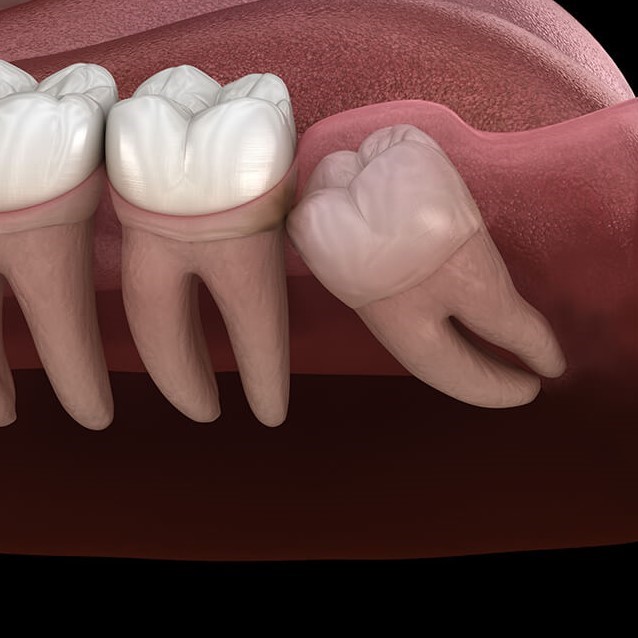

Nhổ răng khôn

Răng khôn mọc lệch, răng khôn ngọc ngầm, gây ra tình trạng đau đớn cần phải nhổ bỏ